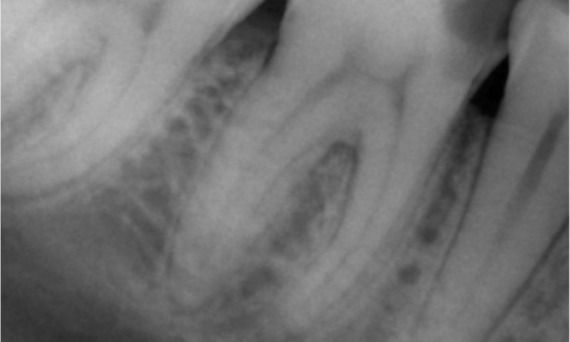

"I chose TruNatomy to be able to preserve as much dentin as possible to overcome occlusal load and increase the longevity of the tooth." - Dr. Abuelezz

Before: Upon examination, there was a caries lesion related to the lower right first molar. Radiographic examination revealed proximity of the lesion to the pulp horn and combining it with the chief complaint, a final diagnosis of chronic irreversible pulpitis was concluded.

After: Access cavity was done as conservative as possible. TruNatomy was the system of choice due to the young patient’s age. We needed to preserve dentine as much as possible to increase the tooth ability to overcome occlusal load and increase the longevity of the final restoration.

Cairo, Egypt